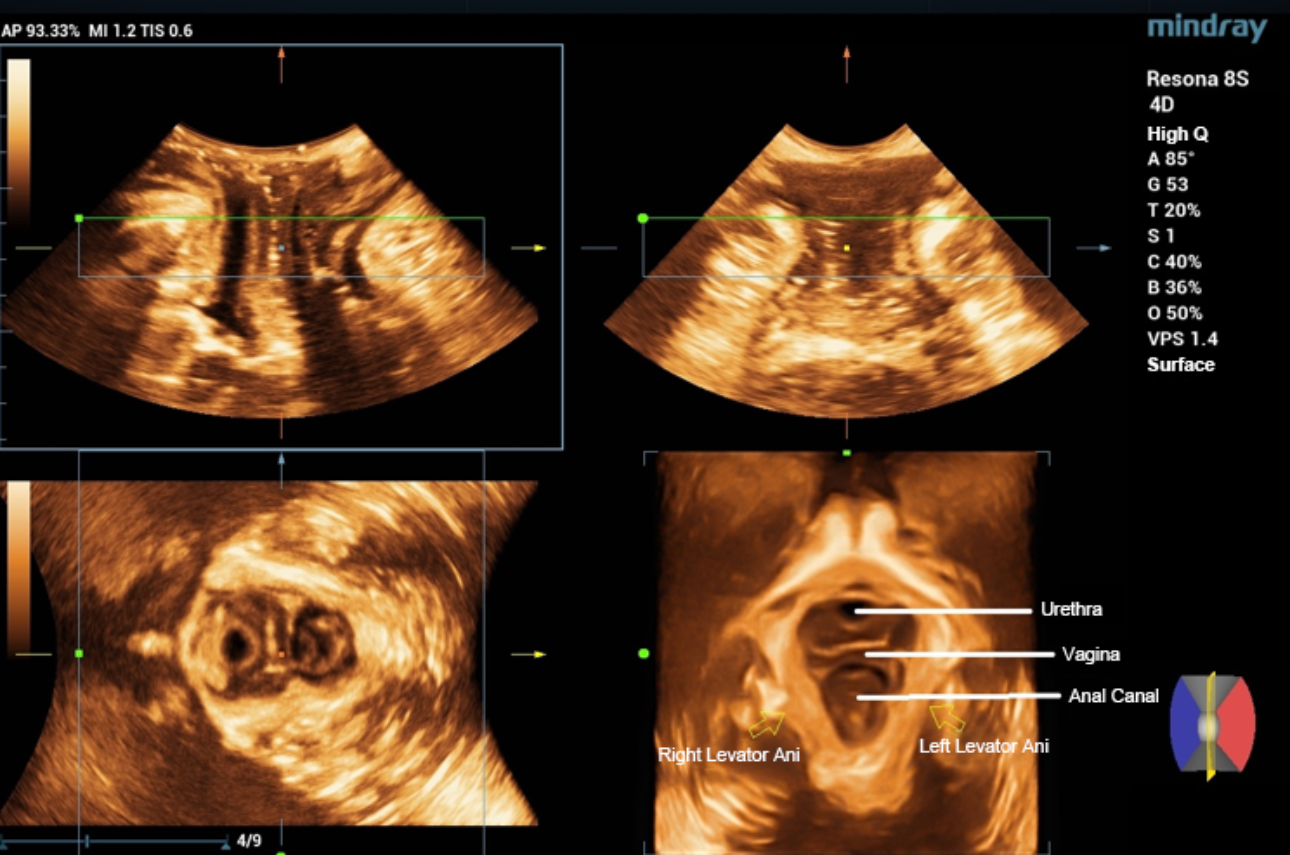

levator-trauma-fig3-pc

형상 1. 항문거근의 골반기저근 초음파 볼륨 영상